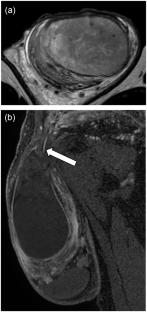

Transverse testicular ectopia (TTE) is a variant of ectopic testis in which both testes are located in the same scrotum. Persistent Müllerian duct syndrome (PMDS) is a congenital anomaly characterized by the retention of Müllerian duct remnants in males. TTE is a characteristic clinical finding in PMDS. This case report describes a patient in his 50s who was diagnosed with PMDS based on TTE findings and a pelvic structure suggestive of a Müllerian duct remnant. Computed tomography (CT) and magnetic resonance imaging (MRI) revealed the normal left testis within the left scrotum. The soft tissue was identified dorsal to the left testis, supplied from branches of bilateral internal iliac arteries. Additionally, a rod-like structure was observed in the left pelvis, appearing continuous with the soft tissue in the left scrotum. The right testis, enlarged and torsed, was located cranially within the left scrotum. A cord-like structure extended continuously from this ectopically positioned right testis toward the right inguinal region. Surgical findings revealed a normal left testis and torsion of the right testis. The right testis was removed. Histological examination revealed a seminoma within the right testis, and immunostaining confirmed the presence of attached Müllerian duct remnants. Prior imaging revealed that the right testis was located in the abdominal cavity, indicating that TTE in this case did not occur during testicular descent. In PMDS cases, TTE is believed to result from the traction of one testis by Müllerian duct remnants and the testicular mobility due to an abnormally long gubernaculum, which is a crucial role in normal testicular descent. The findings in this case support this theory and further indicate that TTE can occur even after testicular descent is complete. This report describes a case of TTE with a causative Müllerian duct remnant and a presumed abnormally long gubernaculum identified on imaging, which contributes to the understanding of this rare condition.